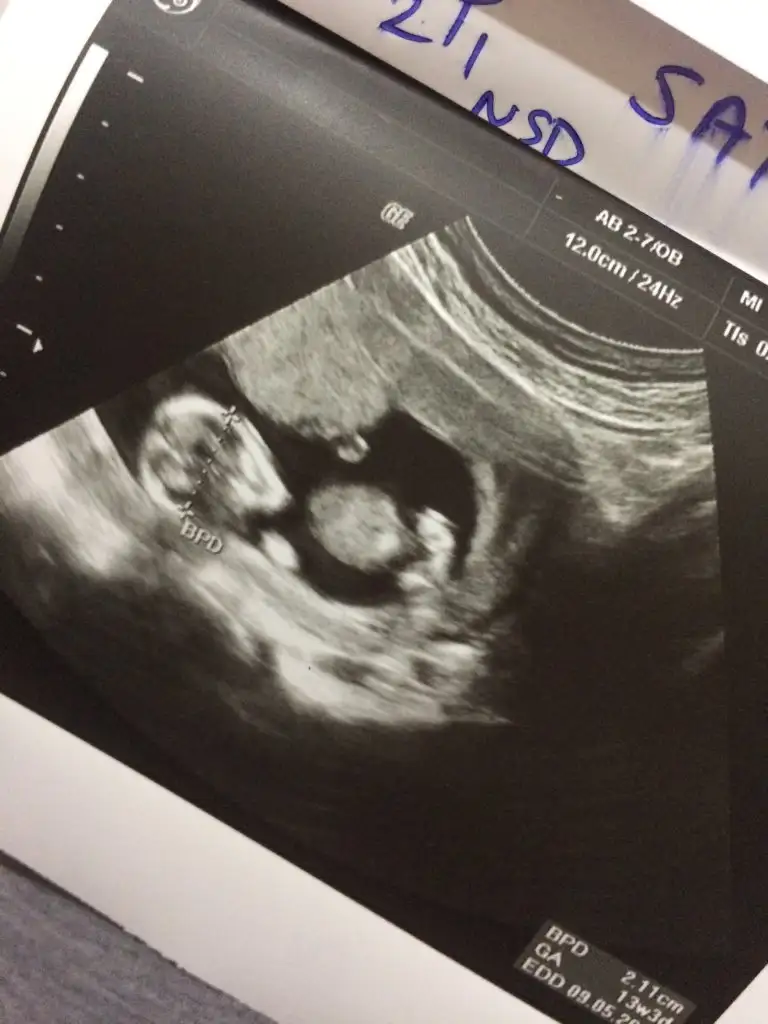

11. Haftada kız gibi dedi. 12 de nubu biraz kalkmıştı erkek de olabilir dedi. 15 te %100 kız dedi değişirse kıyafetlerini ben alırım dediSize 12.haftada doktor, erkek mi dedi?

12.haftada bana da erkek dedi dr, pipi fotosu verdi ben seçemedim nubunu..umarım bu gidişimde kız der..11. Haftada kız gibi dedi. 12 de nubu biraz kalkmıştı erkek de olabilir dedi. 15 te %100 kız dedi değişirse kıyafetlerini ben alırım dedi16 da da hala kız dedi